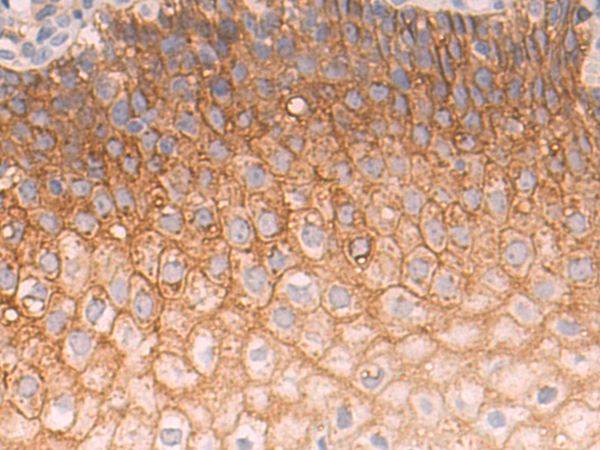

分类: 科研抗体货号: P10690别名: TIM; KIM1; TIM1; CD365; HAVCR; KIM-1; TIM-1; TIMD1; TIMD-1; HAVCR-1应用: WB,IHC反应种属: Human